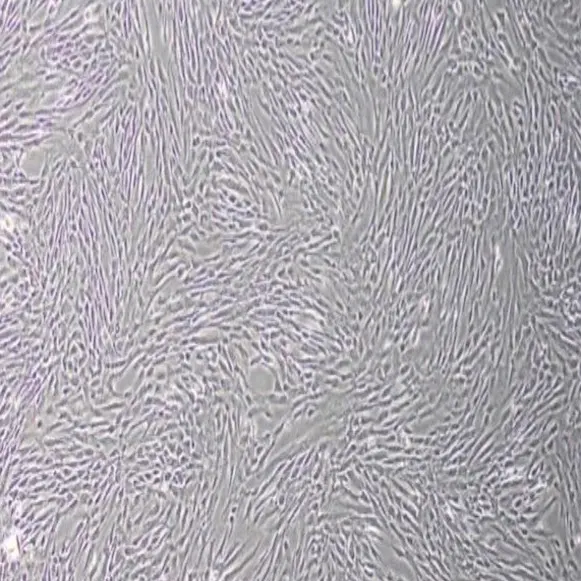

2) ใช้เทคโนโลยีการเพาะเลี้ยงเพิ่มจำนวนในห้องปฏิบัติการ

Highly active NK Cell therapy ซึ่งจะช่วยเพิ่มภูมิคุ้มกันของคุณให้อยู่ในระดับที่ดีขึ้น ซึ่งเป็นวิธีการที่สมบูรณ์แบบในการฟื้นฟูระบบภูมิคุ้มกันที่อ่อนแอลงเนื่องจากความเจ็บป่วย อายุที่เพิ่มมากขึ้น หรือความเครียด

NK Cell ที่ถูกกระตุ้นการทำงานแล้ว เพิ่มเข้าสู่ระบบภูมิคุ้มกันของคุณ ซึ่งจะช่วยลดจำนวนของเซลล์ที่กลายพันธ์ุในร่างกายของคุณและช่วยป้องการเจริญเติบโตของมะเร็งนอกจากนี้ยังช่วยสร้างความแข็งแรงให้กับร่างกาย ที่เกิดความเสียหายจากการรักษามะเร็ง เช่นการฉายรังสี โดยเป็นการไปเพิ่มภูมิคุ้มกันโดยรวมของคุณ

2) สำหรับ Mesenchymal Stem Cell;MSC สามารถเก็บได้จาก Placenta saving หรือ Stem Cells from CORD TISSUE เนื่องจากมีแหล่งกำเนิด Stem cell เยอะมีศักยภาพสูง และไม่เจ็บ อาจเรียกว่า Umbilical Cord Tissue Collection Process หรือ Wharton’s Jelly Collection Procedure ซึ่งในปัจจุบันมีเพียงธนาคารสเต็มเซลล์ไม่กี่แห่งเท่านั้นที่สามารถเก็บเซลล์ชนิดนี้ได้ เช่น MEDEZE GROUP

นอกจากนี้ ยังสามารถเก็บได้จาก Adipose tissue stem cell ซึ่งประกอบไปด้วย สเต็มเซลล์ปริมาณมากเป็นวิธีที่ไม่ทำให้บาดเจ็บมาก และสร้างเซลล์สเต็มเซลล์ที่เป็นของตัวเอง ซึ่งในปัจจุบันมีเพียงธนาคารสเต็มเซลล์ไม่กี่แห่งเท่านั้นที่สามารถเก็บเซลล์ชนิดนี้ได้ เช่น MEDEZE GROUP

โดยที่การเก็บสเต็มเซลล์นั้น หากเก็บถูกต้องผ่านห้องปฏิบัติการที่น่าเชื่อถือได้ มีประสิทธิภาพและควบคุมโดยแพทย์ผู้เชี่ยวชาญ การเก็บสเต็มเซลล์ถือว่าเป็นขั้นตอนที่ปลอดภัย ไม่มีผลข้างเคียง ได้เซลล์สเต็มเซลล์ที่มีคุณค่า มีประสิทธิภาพและสามารถนำไปใช้งานได้